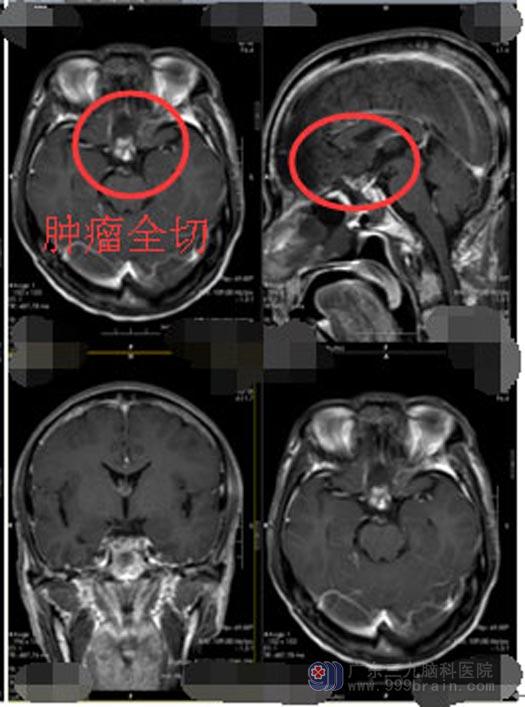

来到广东三九脑科医院神经外五科后,黄大爷进行了进一步的检查,检查结果提示:1,前颅底占位病变,考虑脑膜瘤;2,垂体后叶Rathke`s囊肿。神经外五科的医生团队经过讨论,一致认为可以采取经鼻蝶手术切除肿瘤,不但手术创伤小、恢复快、而且并发症也少。得到大爷和家属的同意后,2019年10月10日实施了“内镜经鼻蝶鞍结节脑膜瘤+鞍区囊肿切除术”,手术过程很顺利,利用导航精确定位,将两处占位病变全部切除,解除了肿瘤对视神经的压迫。术后病理诊断也于术前诊断一致:1,(鞍结节)脑膜皮细胞型脑膜瘤,WHOI级;2,结合临床及影像,符合(鞍区)Rathke囊肿。

▲手术后